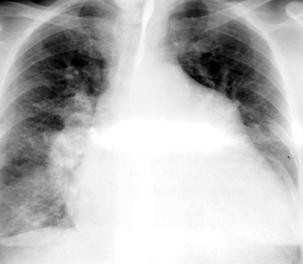

4.Rx

-identic cu DSV